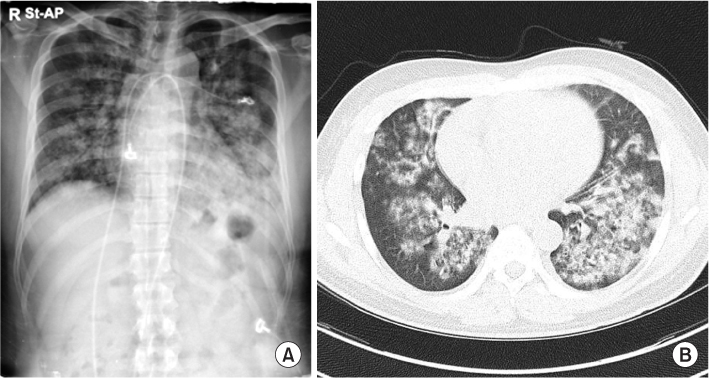

3 -, 14.3 mEq/L). A peripheral blood smear indicated normocytic normochromic anemia with schistocytes, anisopoikilocytosis, and polychromasia, and thrombocytopenia compatible with microangiopathic hemolytic anemia such as thrombotic thrombocytopenic purpura and hemolytic uremic syndrome, or reactive conditions such as infection and inflammation. Fundoscopic examination showed retinal vein dilation, retinal artery thinning, cotton wool spots, papillary exudate, and macular pucker consistent with hypertension. Plasma renin activity, and aldosterone, vanillylmandelic acid, metanephrine, epinephrine, and norepinephrine levels were within normal limits. Autoantibodies, including anti-glomerular basement membrane, anti-nuclear, anti-ds-DNA, anti-ss-DNA, anti-Sm, anti-SS-B, anti-SS-A, and anti-RNP antibodies, were negative. Additionally, anti-neutrophil cytoplasmic anti-body was negative. Complement levels were within normal limits, and the C-reactive protein level was elevated at 6.79 mg/dL. Chest radiography showed bilateral patchy infiltrating shadows with consolidation (

Fig. 1A). Additionally, chest computed tomography showed multifocal ill-defined nodular opacities in both the lungs. A high number of consolidations and hemoptysis on computed tomography indicated the presence of pulmonary alveolar hemorrhage (

Fig. 1B). Echocardiography showed moderate concentric left ventricular hypertrophy and grade 1 left ventricular diastolic dysfunction. Abdominal computed tomography did not reveal adrenal adenoma, hyperplasia, or renal artery stenosis. Additionally, bronchoscopy was not performed. Based on the findings, he was clinically diagnosed with malignant hypertension, and antihypertensive therapy and hemodialysis were started with packed red blood cell transfusion. His blood pressure was reduced with nifedipine, carvedilol, olmesartan, and minoxidil. After blood pressure control, renal biopsy was performed on day 7 of hospitalization to examine the underlying disease. Light microscopy showed up to 15 glomeruli in the renal cortical tissue. The glomeruli showed globally wrinkling, thickening, replication of the basement membrane, and occasional collapsing sclerosis in the glomerular tufts. Additionally, the interlobular and arcuate arteries and arterioles showed intimal fibrosis and multiple layers of periodic acid-Schiff-positive material (‘onion-skin’ changes) (

Fig. 1A chest radiograph and computed tomography image. (A) The radiograph shows bilateral patchy infiltrating shadows with consolidation. (B) The computed tomography image shows multiple and asymmetrical alveolar hemorrhage shadows.